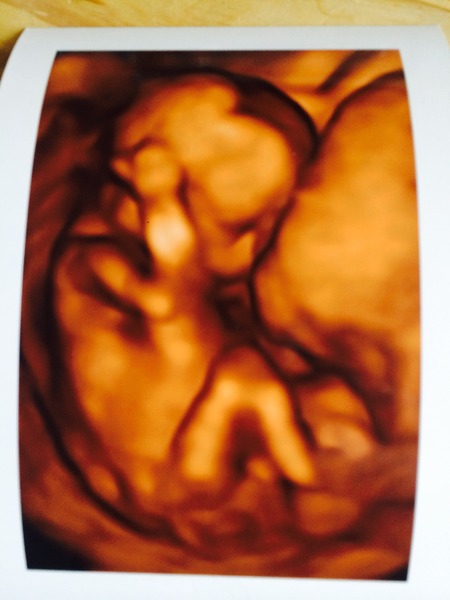

I'm new to the tread, I had a private scan yesterday (16wk) and it was well worth the money, so lovely seeing how baby has changed and found out we are having a baby girl. I'm just so impatient and couldn't wait until 27th April. I've tried to attach the pic hope it works x

Welcome soontobemummyto5! U have my 20 week scan in 27th April as well. Also had a private 16 week scan at the weekend, found out we're having a girl too :-) absolutely delighted! Your scan pic is amazingly clear. Is that the placenta the baby's head is resting on?

Yes she hiding behind the placenta, I tried skipping round the room jumping up and down but she wouldn't budge, it's the first private scan we've had and was surprised at how clear the pics were. It's made it all seem real now as have no bump at all and no real symptoms other than very occasional sickness

What an amazing scan pic, so cute!!